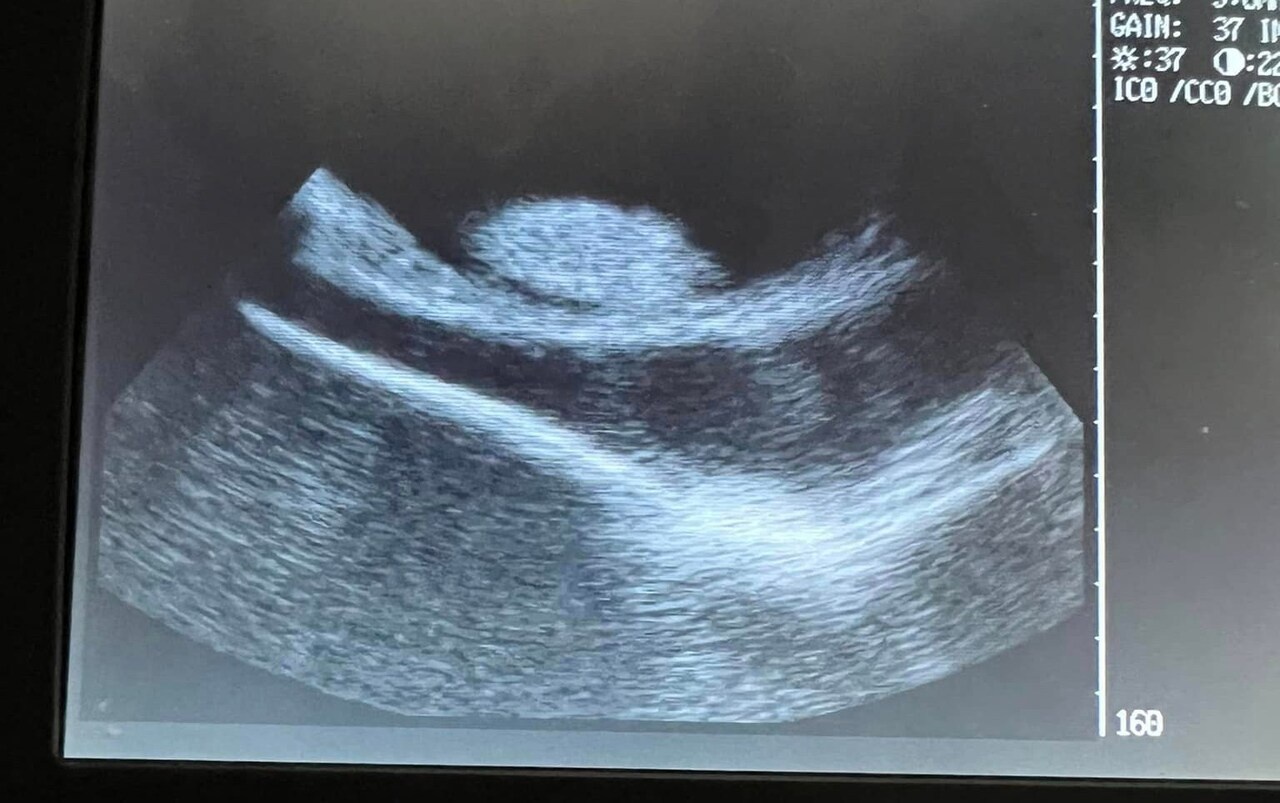

Nhóm nghiên cứu tại thủy cung đã siêu âm và gửi kết quả cho các nhà khoa học. Họ xác nhận rằng Charlotte đang mang trứng. Những lần siêu âm tiếp theo thậm chí còn cho thấy những chiếc đuôi nhỏ đang vẫy.

Siêu âm cho thấy Charlotte có thể sinh nhất nhất 2 con. Ảnh: Aquarium and Shark Lab.